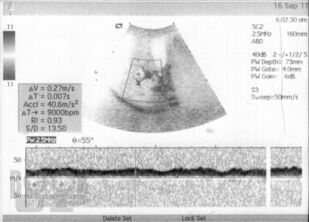

Монография посвящена возможностям малоинвазивного лечения цирроза печени, в т. ч. в стадии декомпенсации с явлениями коагулопатии и тромбоцитопении. Биологические основы эффективности разработанного метода подтверждены в эксперименте и клинике. Доказано, что введение криопреципитата в ткань печени при циррозе вызывает регенерацию функционально сохранных участков паренхимы с образованием упорядоченной балочной структуры и сохранением физиологического соотношения элементов паренхимы и стромы органа. Это способствует улучшению клинико-лабораторных данных и морфологической картины заболевания, в т. ч. улучшению внутрипеченочного кровотока и снижению явлений портальной гипертензии.